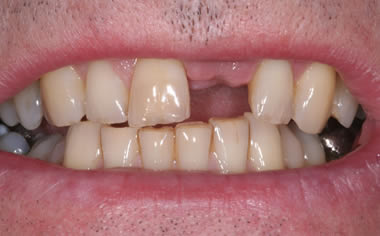

More front teeth replaced by dental implants

Case Three (4 images)